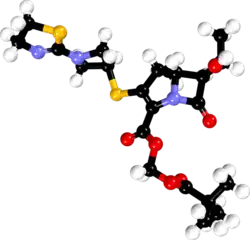

| 3D model (JSmol) | |

Tebipenem (brand name Orapenem) is a broad-spectrum orally-administered antibiotic, from the carbapenem subgroup of β-lactam antibiotics. It was developed as a replacement drug to combat bacteria that had acquired antibiotic resistance to commonly used antibiotics.[1][2] Tebipenem is formulated as the ester tebipenem pivoxil due to the better absorption and improved bioavailability of this form.[3] It has performed well in clinical trials for ear infection and looks likely to be further developed in future.[4] It is only marketed in Japan.[5] Tebipenem is the first carbapenem whose prodrug form, the pivalyl ester, is orally available.[6]